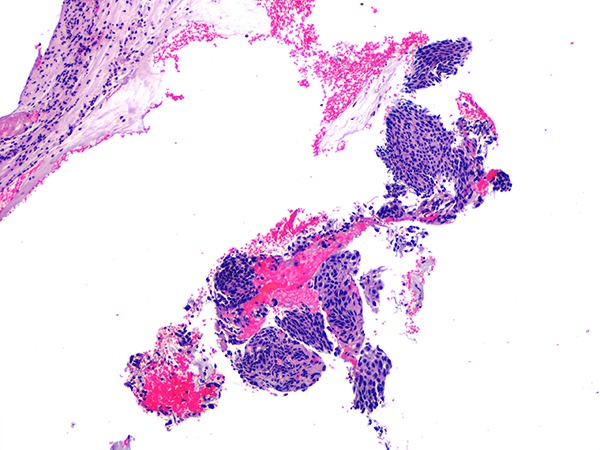

Case 1

Soft Bx CIN 2 10x - Low Power